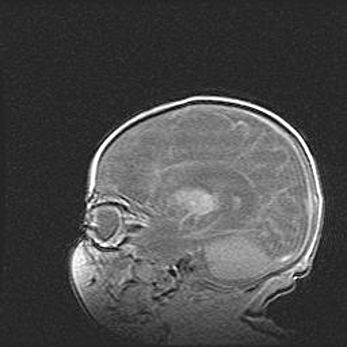

Аномалия Денди-Уокера. Признаки гипоплазии мозолистого тела.

Возраст: 5 месяцев 3 дня

Вес: 5550 г

Пол: мужской

Окружность головы: 39 см

Срок гестации: 40 недель

Аномалия Денди-Уокера – это порок развития головного мозга, для которого характерна триада симптомов: гипотрофия или аплазия червя мозжечка и/или полушарий мозжечка, расширение четвёртого желудочка с формированием ликворной кисты задней черепной ямки, гипертензионная гидроцефалия различной степени.

Гипоплазия мозолистого тела относится к дефектам внутриутробного этапа развития мозговой ткани, возникающим в процессе закладки структур головного мозга, что происходит на начальных этапах развития эмбриона.